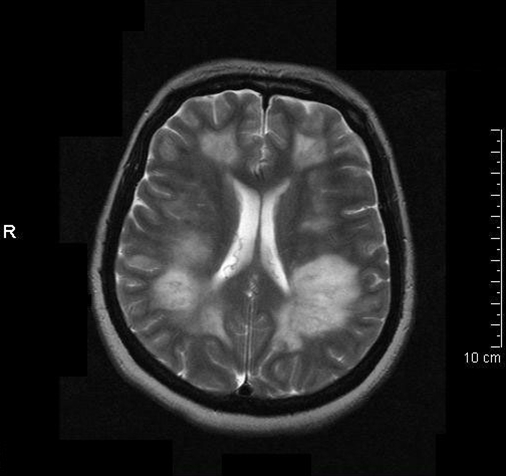

Информация о диссеминированном рассеянном энцефаломиелите